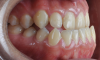

Fig 3. Pretreatment dental views of the patient; right lateral view (Fig 3), frontal view (Fig 4), and left lateral view (Fig 5).

Figure 3

Fig 10. Postsurgical orthodontics for bite settling after the surgical procedure. Surgery for this patient consisted of maxillary surgical advancement, mandibular surgical asymmetric setback, and genioplasty (chin correction). Note the anterior and posterior crossbite was corrected and a class I occlusion was obtained.

Figure 10